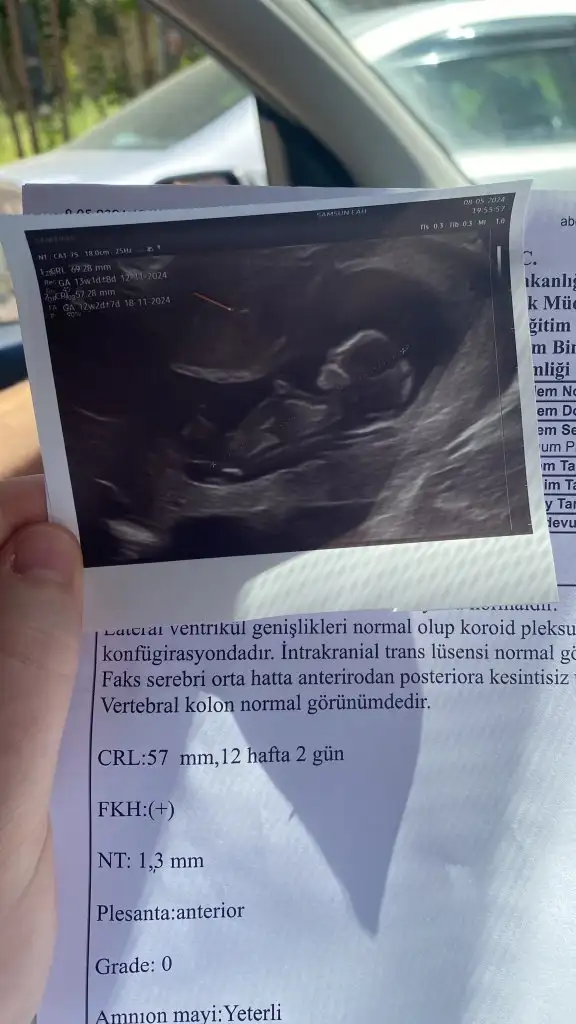

Siz anlıyorsunuz galiba banada yorum yapabilir mısınız bugün doktora gittim 12 haftalık ama küçük daha zamanı var dedi Meraktan catliyorumCanım erkek gibi

Erken diyorlar ama bazı doktorlarda ikili testte söylüyor.Acaba kız bebek olduğu için mı söylemek istemiyorlar.Bende aynı 12 +2de ikili test yaptırdın,3.gebeliğim ve 16.haftaya anca belli olur dediler çok merak ediyorum.Benimki de 12 haftalik doktor daha erken demisti gorunmuyor dedi. 4. Ay soylermis.